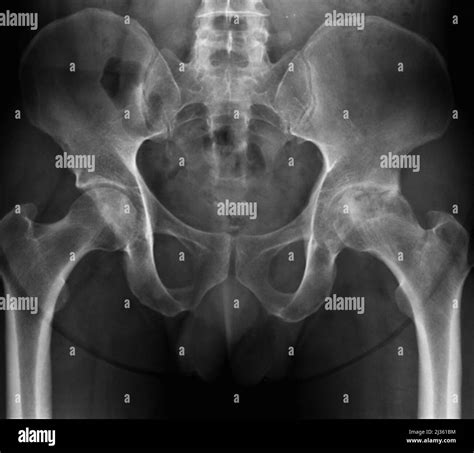

Hey guys, let’s dive into something that affects a ton of people, especially as we get older: osteoarthritis . You might have heard it called “wear and tear” arthritis, and it’s basically what happens when your joints start to feel the squeeze. The biggest bummer about osteoarthritis is that it’s the primary cause of bone rubbing on bone inside your joints. Imagine your joints as smooth, well-oiled hinges. In osteoarthritis, that smooth cartilage cushioning the ends of your bones wears away. Without this protective layer, your bones start to grind against each other directly. It’s like running a rusty hinge without any grease – painful, stiff, and definitely not smooth! This condition doesn’t just pop up overnight; it’s usually a slow and progressive process. The key players here are your joints, which are the crucial connections between your bones that allow you to move. Think about your knees bending, your hips swiveling, or your fingers flexing – all thanks to these incredible joint structures. Inside these joints, the ends of your bones are covered with a smooth, slippery tissue called cartilage. This cartilage acts like a shock absorber and ensures that your bones glide effortlessly against each other. But when osteoarthritis sets in, this cartilage begins to break down. It gets rough, frayed, and eventually wears away completely. What’s left is the dreaded bone rubbing on bone scenario. This friction leads to inflammation, pain, stiffness, and a significant reduction in your joint’s range of motion. The most commonly affected joints include the knees, hips, hands, and spine, but it can impact any joint in your body. Understanding this fundamental process is the first step in managing this condition and finding ways to live a fuller, less painful life. We’ll explore the causes, symptoms, and most importantly, the strategies you can use to combat the effects of osteoarthritis and keep your joints moving as smoothly as possible, even when the cartilage isn’t cooperating.

So, to really get a handle on bone rubbing on bone , we need to understand what osteoarthritis actually is. At its core, osteoarthritis (OA) is a degenerative joint disease. This means it’s a condition where the protective cartilage that cushions the ends of your bones within a joint gradually wears down over time. Think of cartilage as the slick, rubbery material that covers the ends of bones where they meet to form a joint. Its job is super important: it allows bones to glide smoothly over each other, absorbing shock and preventing friction. In a healthy joint, this cartilage is smooth, flexible, and abundant. But with OA, this cartilage starts to break down. It can become rough, frayed, and thin, and in severe cases, it can wear away completely. When that happens, you’re left with direct contact between the bones themselves. This is the ‘bone rubbing on bone’ sensation that causes so much pain and discomfort. It’s not just the bones, though. As the cartilage deteriorates, other changes happen within the joint. Bone spurs, which are extra bits of bone, can develop along the edges of the bones. The tissues lining the joint, called the synovium, can become inflamed. The ligaments and tendons surrounding the joint can also be affected, leading to instability and weakness. All these factors contribute to the hallmark symptoms of OA: pain, stiffness, swelling, and a decreased ability to move the joint. It’s a complex process, and while ‘wear and tear’ is a common way to describe it, it’s more than just simple overuse. It involves a combination of mechanical stress and biological processes that lead to the breakdown of joint tissues. The result is a joint that doesn’t function as it should, making everyday activities feel like a monumental effort. We’re talking about everything from walking and climbing stairs to simply gripping an object or turning a doorknob. The impact on quality of life can be profound, which is why understanding the condition and its mechanisms, like that painful bone rubbing on bone friction, is so critical for finding effective management strategies.

Spotting the early signs of osteoarthritis is key, especially before you get to the severe bone rubbing on bone stage. The symptoms often develop gradually, so you might dismiss them at first. But knowing what to look for can help you seek help sooner and manage the condition more effectively. The most common and telling symptom is joint pain . This pain typically worsens with activity and improves with rest. It might start as a dull ache or a burning sensation in the joint. As the condition progresses and the cartilage wears thin, the pain can become more constant and severe, especially during or after movement. You might feel it when you first wake up, or after sitting for a long time – that’s often called ‘start-up stiffness’. Another hallmark symptom is stiffness . This is particularly noticeable in the morning or after periods of inactivity. You might feel like your joints are ‘stuck’ or difficult to move. This stiffness usually lasts for less than 30 minutes, which helps distinguish it from inflammatory types of arthritis. As the cartilage wears away and bone spurs form, you might also experience loss of flexibility . It becomes harder to move your joint through its full range of motion. Bending your knee or straightening your finger might become a challenge. Some people also report feeling a grating sensation or hearing a cracking sound (crepitus) when they move the affected joint. This is often a direct result of the rough surfaces of the bones and bone spurs rubbing together – that audible confirmation of the bone rubbing on bone phenomenon. Swelling can also occur, especially after increased joint use. The joint might look puffy or feel warm to the touch due to inflammation. In later stages, you might notice tenderness when you press on the joint, and some people even develop bone spurs that can feel like hard lumps around the joint, particularly in the finger joints. If you’re experiencing persistent joint pain, stiffness, or any of these other symptoms, especially in your knees, hips, hands, or spine, it’s definitely worth talking to a doctor. Early diagnosis and management can make a huge difference in slowing progression and maintaining your quality of life, long before the bone rubbing on bone becomes unbearable.